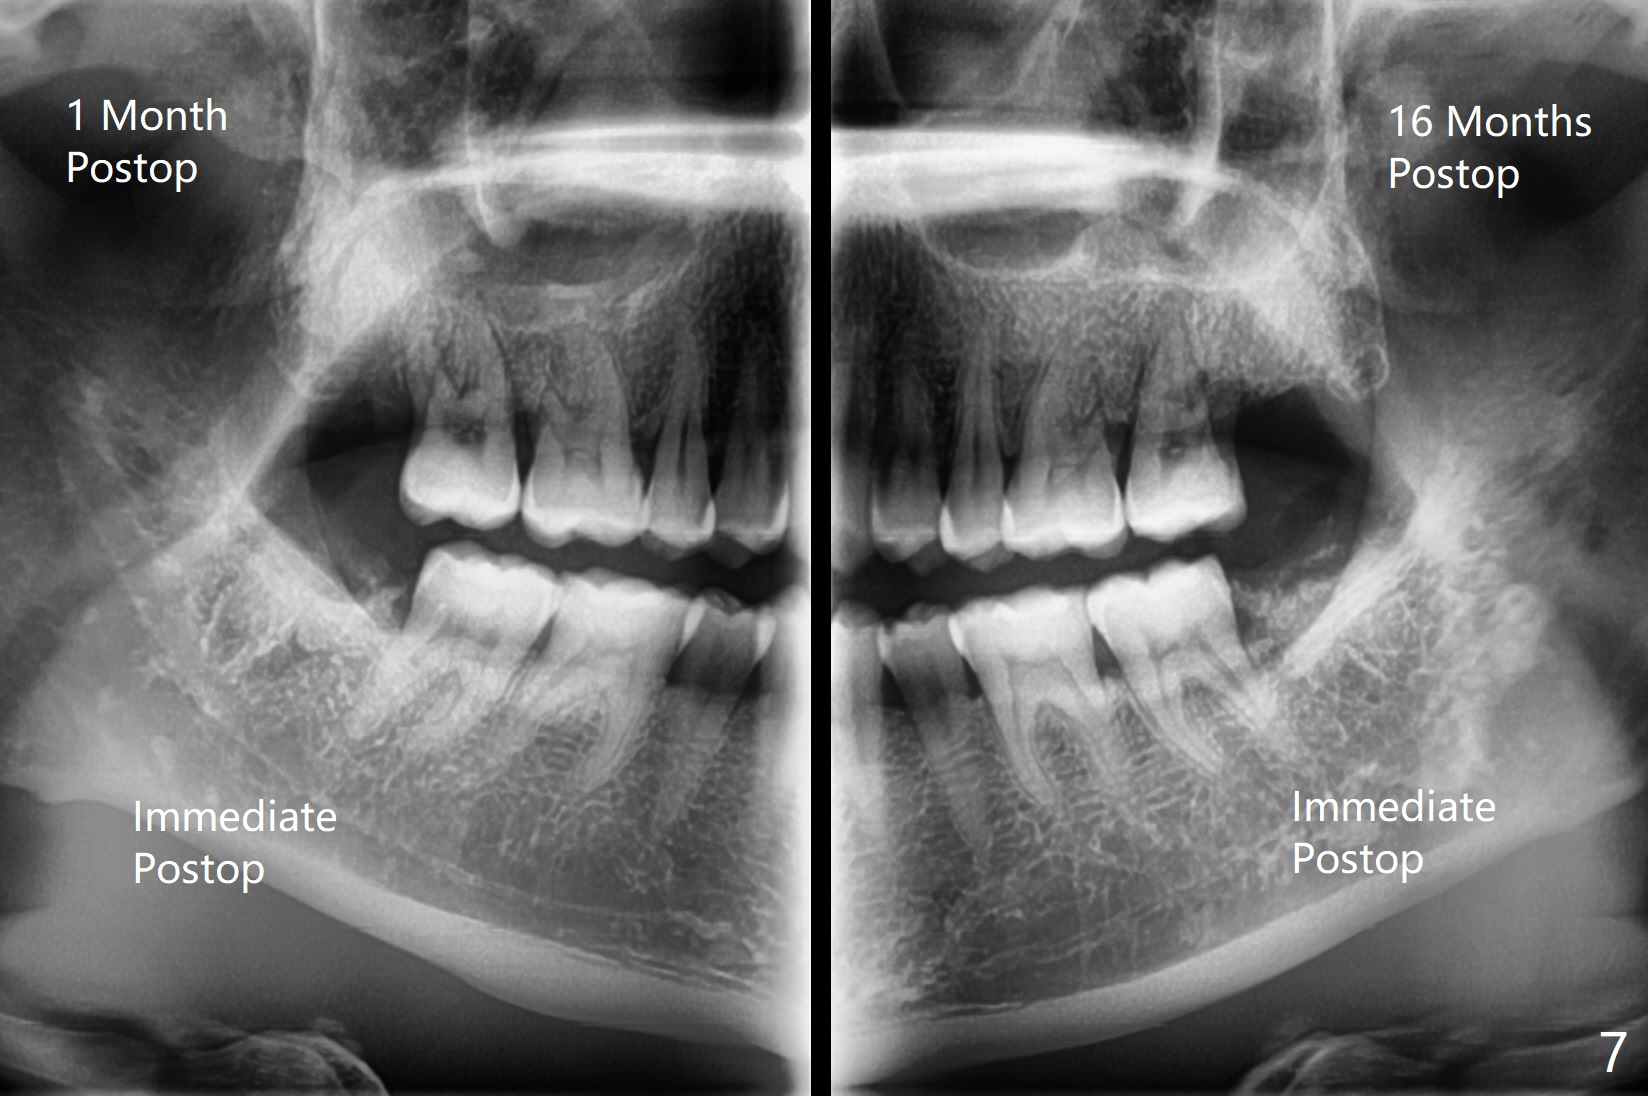

A 35-year-old woman requests extraction of the tooth #1 (food impaction between #1 and 2, Fig.1) and 16 (pain and 6 mm pockets between #15 and 16, Fig.2). In spite of the fact that there is bone loss between #14 and 15 (Fig.3), there is no deep pocket between them. After extraction of #16, SRP is performed in the distal surface of #15 with removal of granulation tissue and application of Endogain. Osteogen plug (Fig.4 O) is placed in the apical and distal portion of the socket of #16 (red dashed line), while allograft (G) against the distal root surface of #15. Finally Collagen plug (C) and 6-month membrane are placed in the opening of the socket, followed by suturing and periodontal dressing. The bone density is high post #1 extraction (Fig.6), related to difficult removal. It appears that bone graft at #16 (^) remains in place 15 months postop. Since no buccal trough is made for extraction, the external oblique ridge is present at #17 and 32 before and after surgery. Bond Apatite is placed with Collagen Plug (Fig.7).